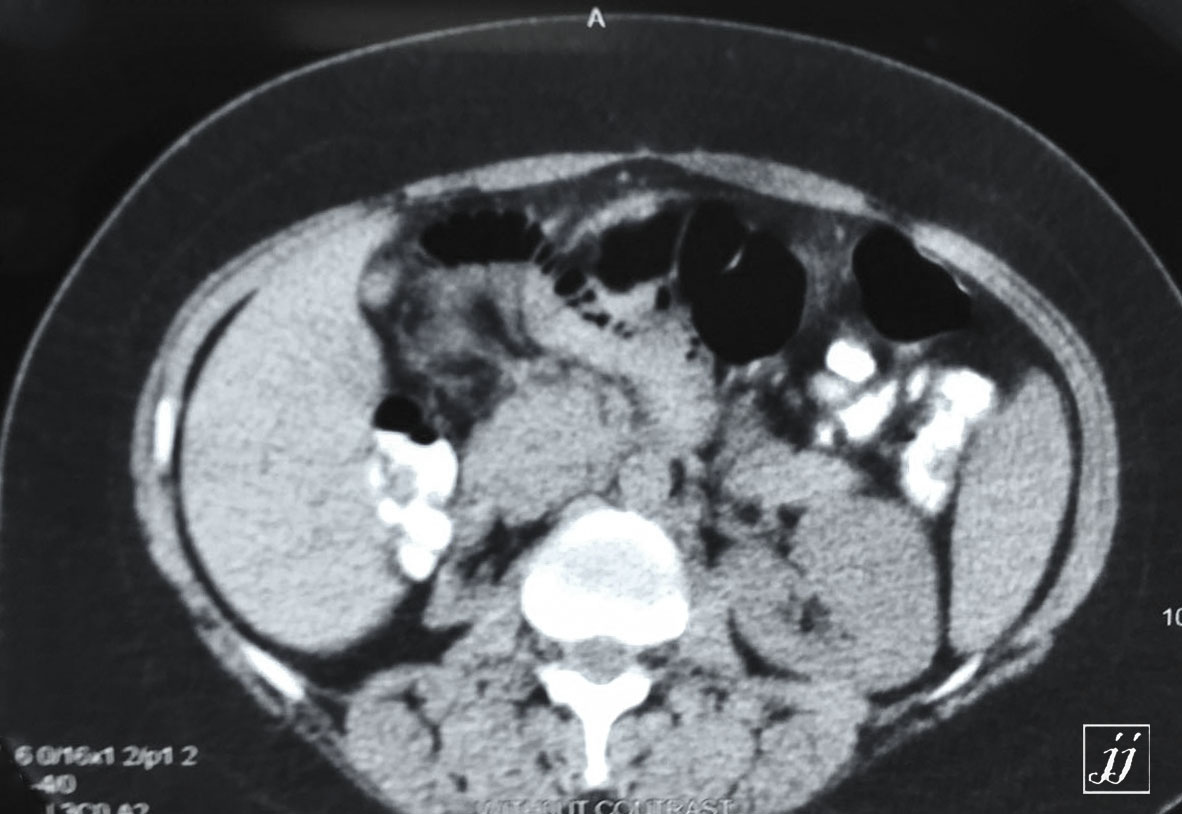

Abdomen- right auto nephrectomy